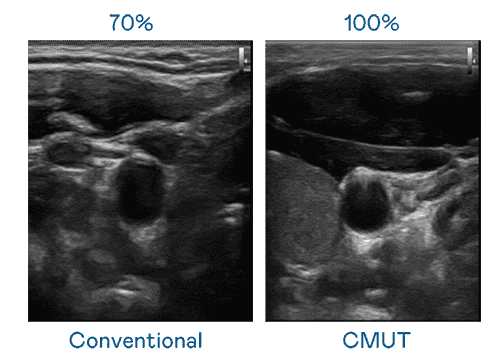

CMUT 技术是一种用电容式微机电元件来产生超音波讯号的技术。。与传统 PZT 压电式技术相比,,CMUT 频宽增加 30%,,,更宽频的超音波讯号让影像解析度大幅提升,,,是实现高影像品质医疗超音波扫描、、、促进精准医疗发展的关键技术。。。。

大频宽带来超清晰影像

超音波影像的解析度高低,,,,首先取决于探头能发出的讯号频宽。。尊龙集团 CMUT 可提供高清晰的超音波讯号,,,提供高频宽、、、、高灵敏度、、影像纹理细节更高的超音波影像,,,协助医护人员缩短影像判读时间及利用精准的医疗影像进行诊断。。。。